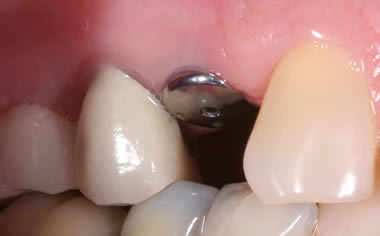

More back teeth replaced by dental implants

Case Three (2 images)

Case Four (4 images)

Case Five (4 images)